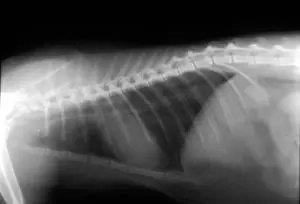

در صورت درگیری مجاری تنفسی تحتانی یا پنومونی، علائمی مانند سرفه شدیدتر، تنگی نفس، تاکی‌پنه و تب واضح‌تر می‌شوند. بچه‌گربه‌ها، گربه‌های مسن و گربه‌های ایمن‌سرکوب‌شده معمولاً علائم شدیدتر و سیر بیماری طولانی‌تری دارند.

• شستشوی برونش‌آلوئولار (BAL) در موارد درگیری ریه و پنومونی

۴. درگیری ریه و پنومونی

در مواردی که شواهد بالینی، رادیولوژیک یا BAL به نفع پنومونی یا درگیری واضح مجاری تنفسی تحتانی باشد، ترکیب دارویی و حمایت تنفسی اهمیت زیادی دارد.

• ترکیب دوکسیکلین با یک فلوروکینولون مناسب (ماربو/پرادو) به مدت ۱۴–۲۸ روز

• اکسیژن‌تراپی در صورت نیاز بر اساس وضعیت تنفسی و اشباع اکسیژن

• نبولایزر با سرم فیزیولوژی ۰.۹٪ هر ۶–۸ ساعت جهت رقیق کردن ترشحات و کمک به تخلیه آن‌ها

• در صورت امکان، انجام BAL برای تأیید عامل، بررسی عفونت‌های همزمان و تنظیم دقیق‌تر درمان